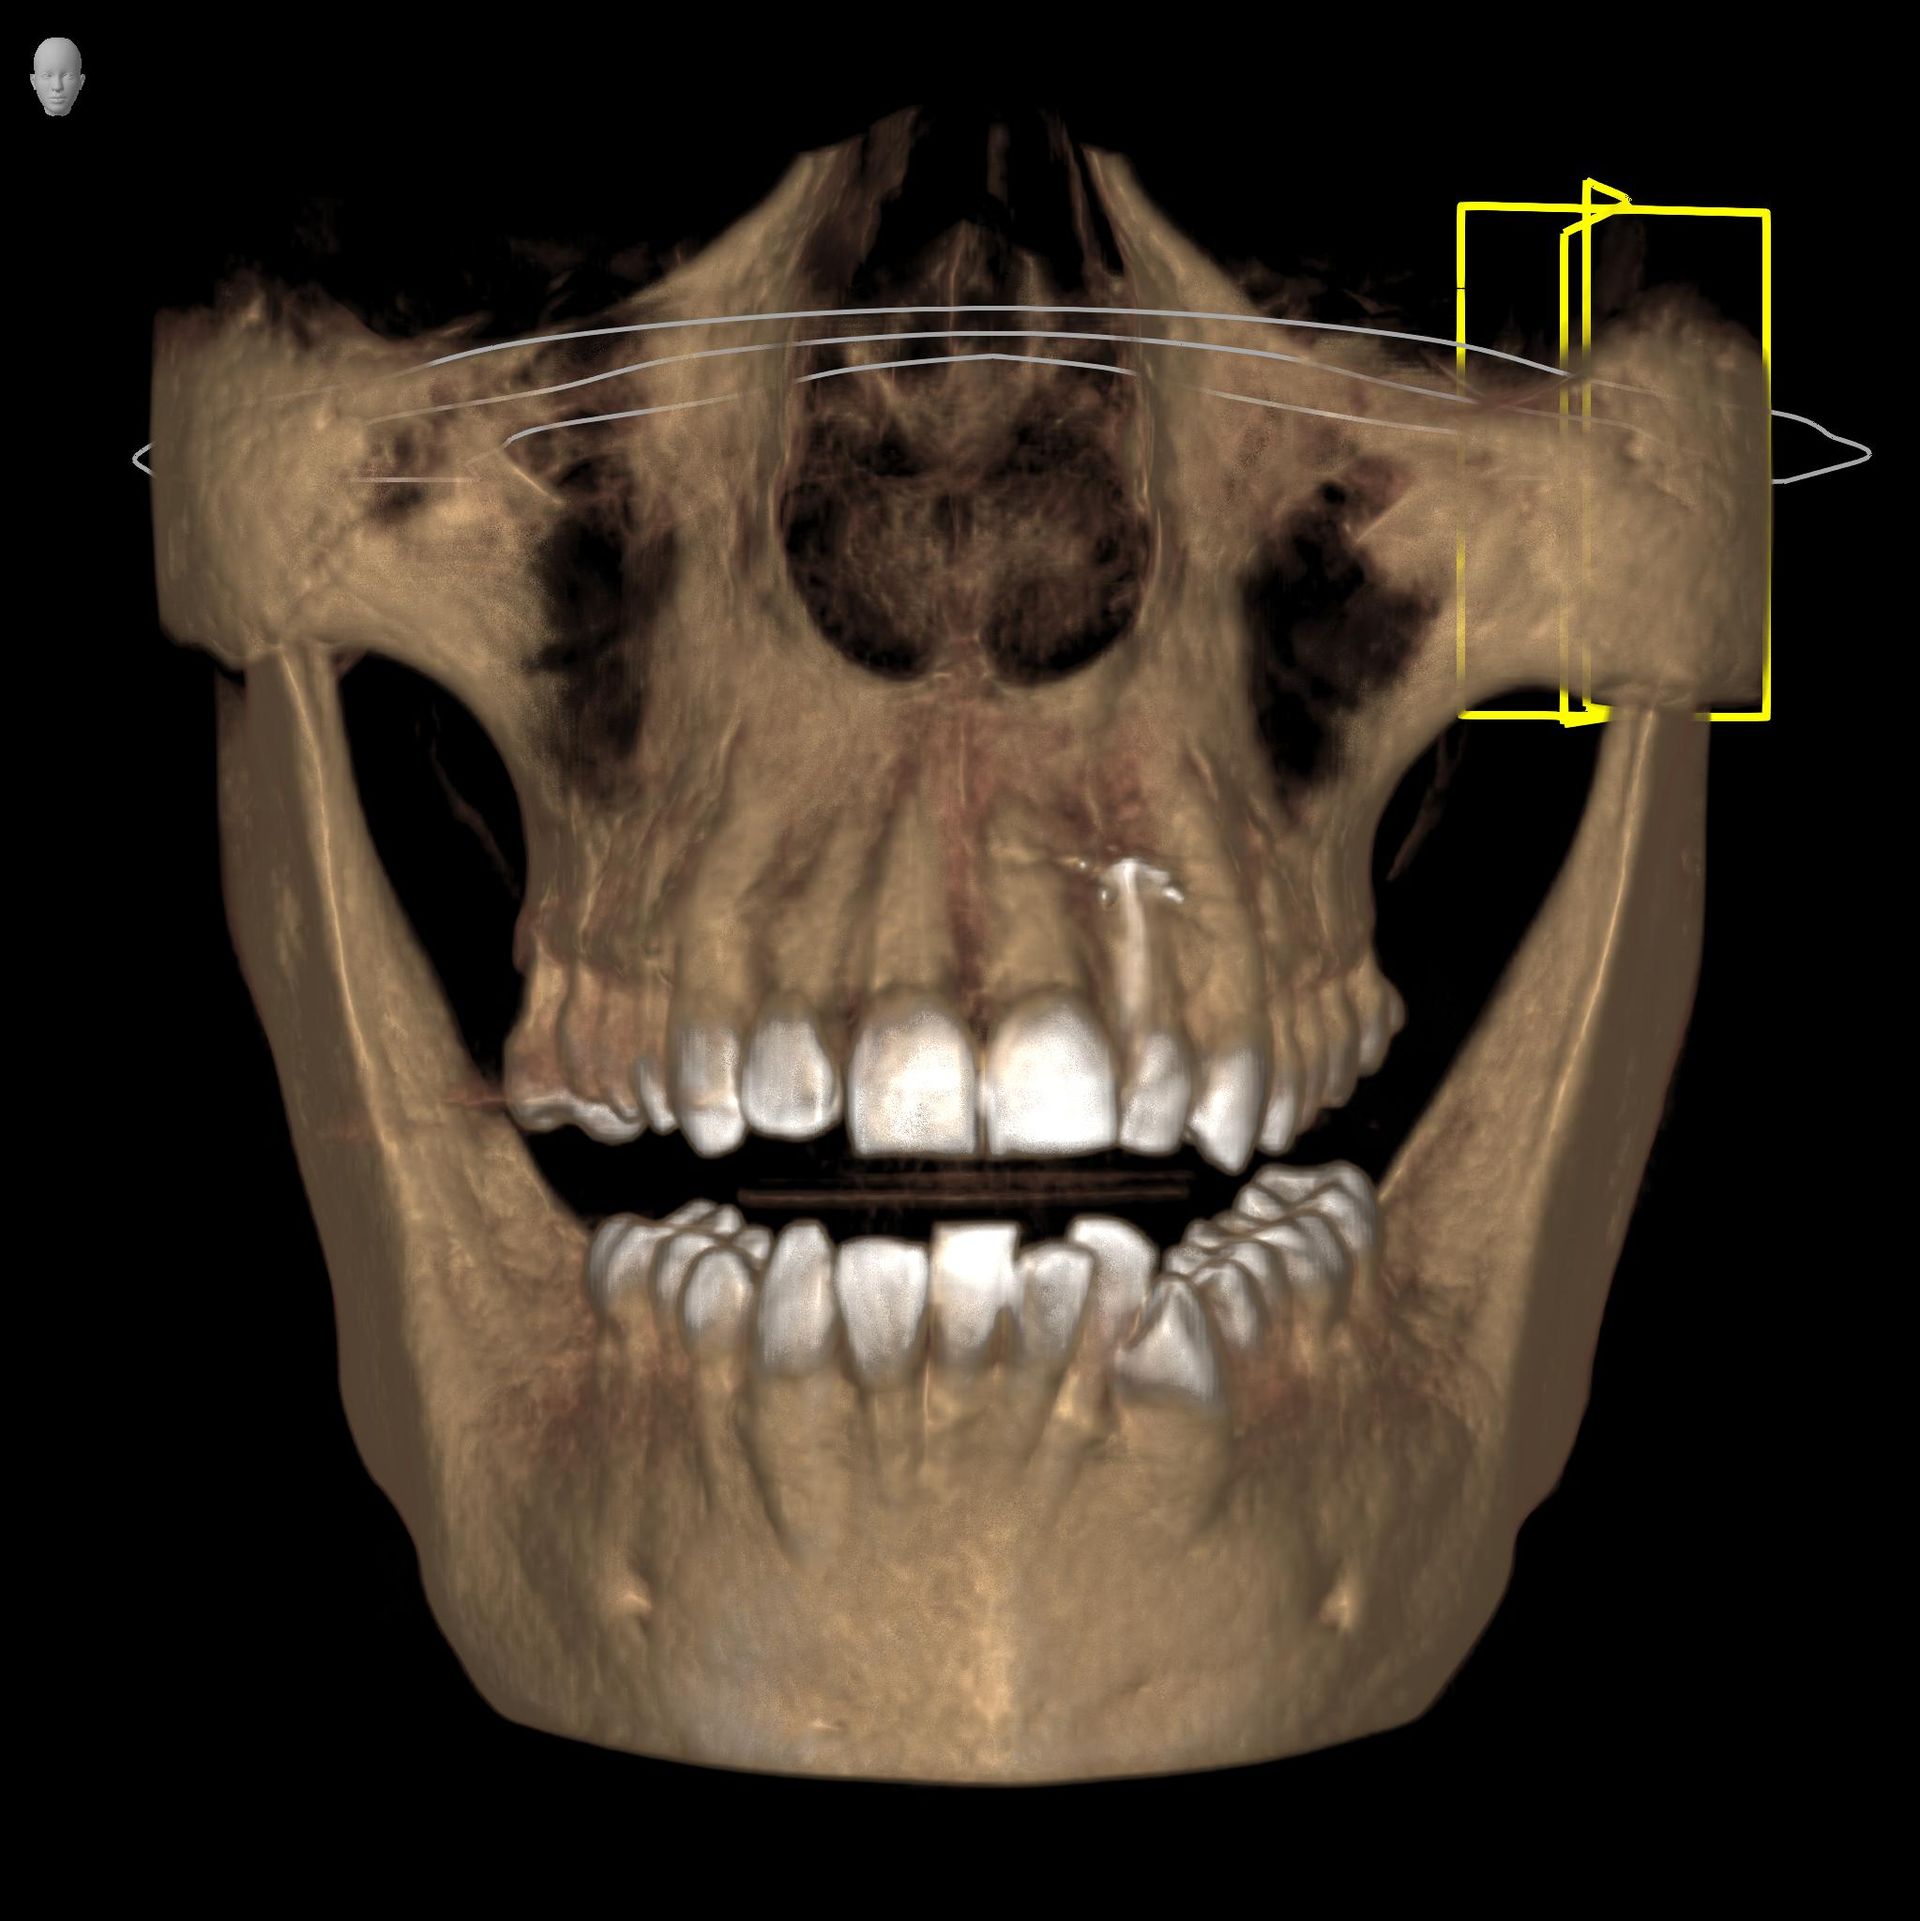

La funzione 3D, permette la visualizzazione completa delle strutture dentarie, ossee, in tre dimensioni, con ottima risoluzione di contrasto per lo studio dei tessuti molli.